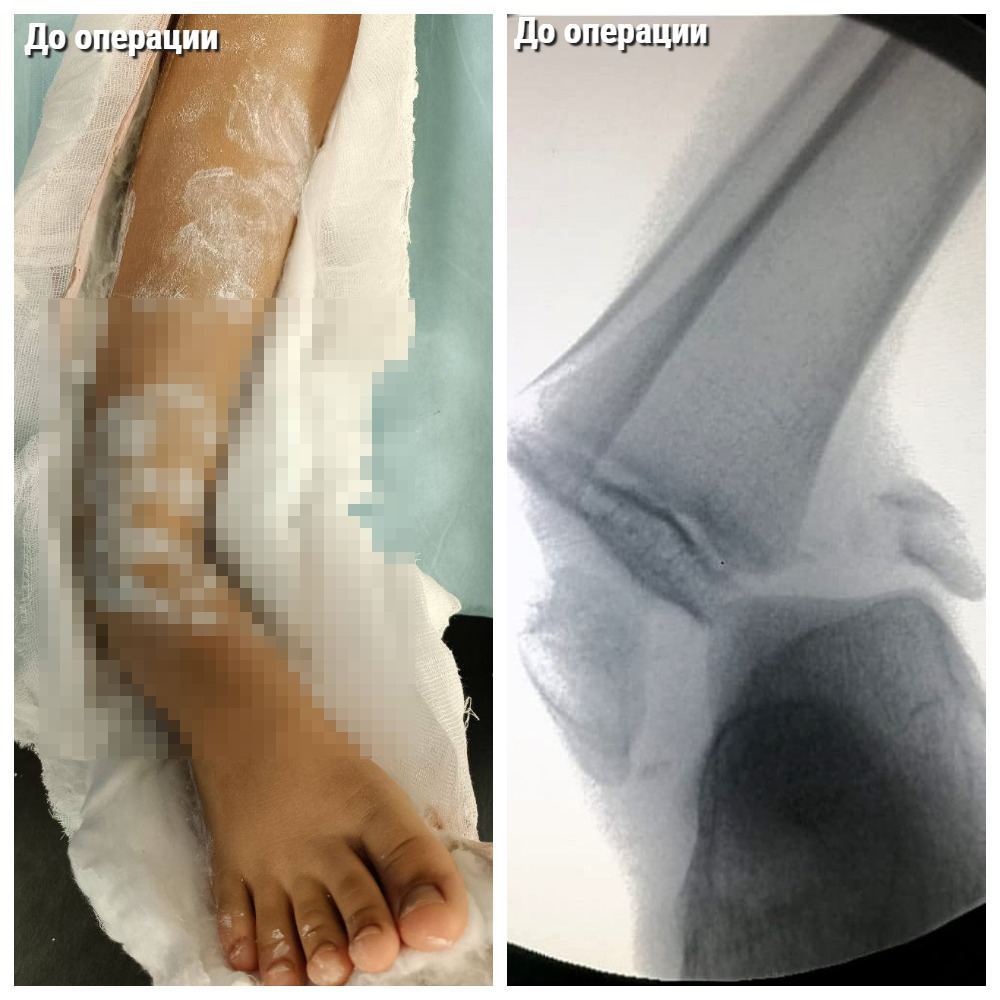

В областную больницу поступил 10-летний ребёнок с вывихом стопы и переломами лодыжек — школьник неудачно упал на батуте, что привело к серьёзным травмам. Ребёнок мог остаться инвалидом: запредельное смещение грозило ишемией конечности.

«Мы сразу взяли ребёнка на операционный стол. Было выполнено хирургическое вмешательство с использованием малоинвазивных техник, чтобы шрамы после операции не напоминали о негативном эпизоде из жизни», — рассказал травматолог МОДКТОБ Виталий Куваев.